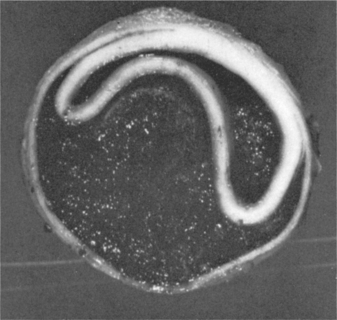

Regardless of the underlying cause, dilated cardiomyopathy results from extensively damaged myocardial muscle fibers and is characterized by cardiac enlargement. The heart ejects blood less efficiently than normal, so that a large volume of blood remains in the left ventricle after systole, which results in ventricular dilation with enlargement and dilation of all four chambers and eventually leads to CHF (Figs. 12-16 and 12-17).

Figure 12-16 A, Cross-sectional view of dilated cardiomyopathy. B, Hypertrophied heart. (From Kinney M: Comprehensive cardiac care, ed 7, St Louis, 1991, Mosby, pp 346, 349.)